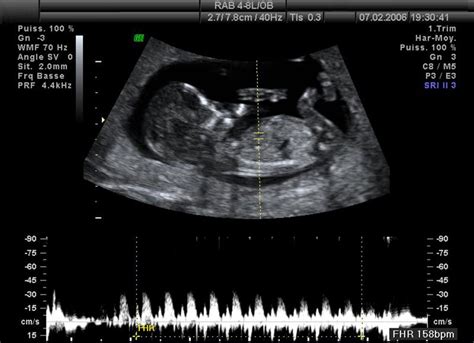

5.-8. týždeň:Toto obdobie je charakterizované rýchlym formovaním orgánov. Vyvíja sa mozog, začínajú byť viditeľné zárodky očí, horných a dolných končatín. V srdci začína kolovať krv. Formujú sa vnútorné orgány ako tráviaci trakt, pľúca, pečeň. Tvárička nadobúda ľudský tvar, vyvíjajú sa uši, pery, nos. Vyvíja sa hmat, čuch a neskôr aj sluch. Na končatinách sa tvoria prsty. Embryo je už viditeľné na ultrazvuku.

9.-12. týždeň:Pohlavné orgány sa vyvíjajú, aj keď pohlavie ešte nie je ultrazvukom rozoznateľné. Oči sú už tvorené, ale prekryté blanou. Ústa sa občas otvárajú a objavuje sa sací reflex. Dieťa je už pohyblivé, vie zovrieť pästičky. Na konci 12. týždňa má plod dĺžku približne 7-9 cm. Hlava tvorí takmer polovicu dĺžky tela. Placenta plne preberá funkciu výživy.